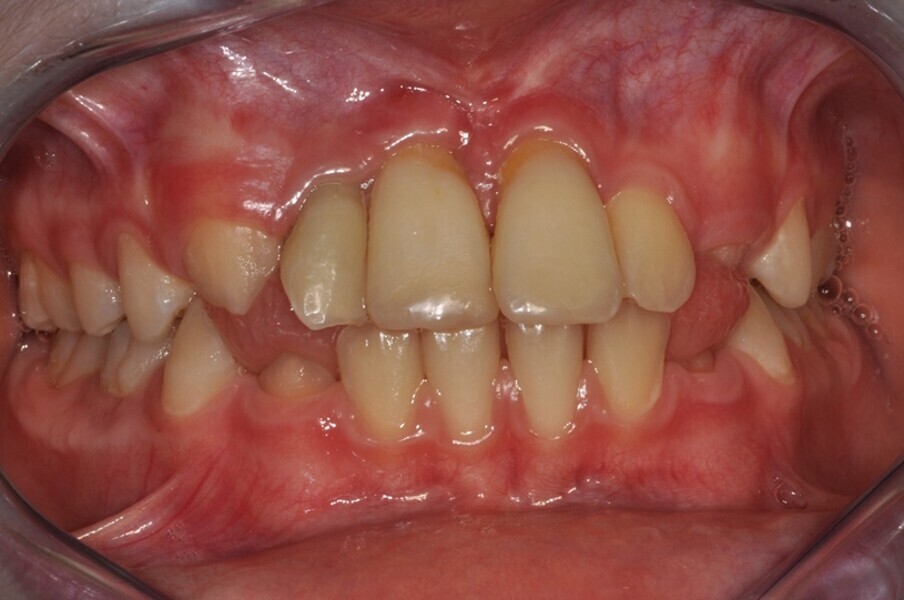

Ryc. 1_Stan miejscowy przed ekstrakcja zębów 11 i 21.